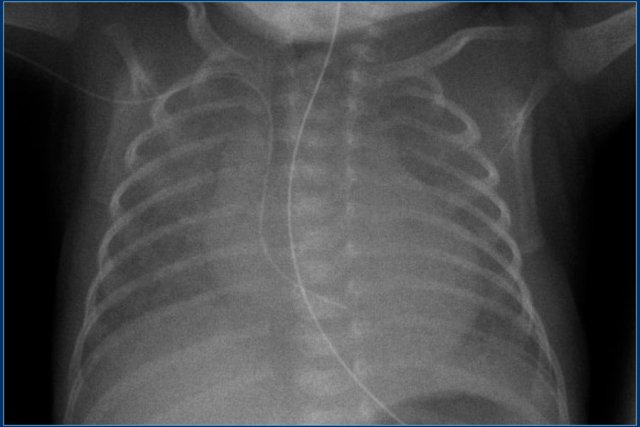

• The umbilical venous line is too deep

• After repositioning the tip is in a good position.

Notice that the endotracheal tube is too deep.